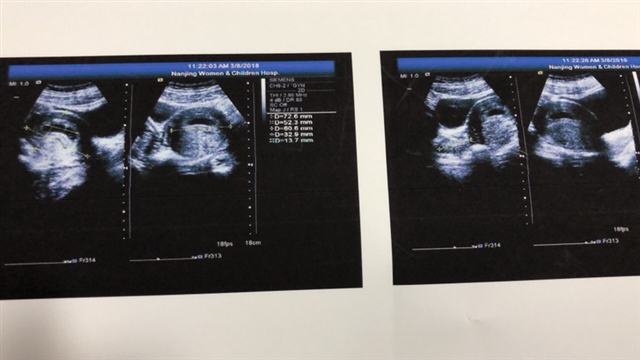

产前检查 B超

孕12周+6天

孕13周+2天